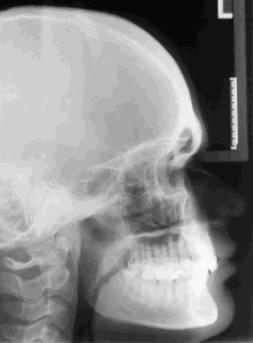

1.) Das Fernröntgenseitenbild (FRS) ist eine seitliche Röntgenaufnahme des Kopfes. Das Röntgenbild gibt Informationen über den Verlauf des Gesichtsprofils, die Lage des Ober- und Unterkiefers relativ zur Schädelbasis sowie die Stellung der Zähne im Ober- und Unterkiefer.

Während des gesamten Wachtums - besonders in der Zeit des Wechselgebisses - gibt diese spezielle Röntgenaufnahme Hinweise auf den knöchernen Aufbau des Gesichtsschädels sowie die Richtung des Schädel- und Gesichtswachstums.

Diese Röntgenaufnahme wird vor allem bei der Planung und Überwachung einer kieferorthopädischen Behandlung benötigt. Die digitale Übertragung der anatomischen Strukturen in ein Analyseprogramm und deren Auswertung gibt wertvolle Hinweise für die Möglichkeiten und Grenzen der Planung einer kieferorthopädischen und auch kiefer-chirurgischen Behandlung.

Die Informationen des Röntgenbildes sind entscheidend bei der Auswahl des richtigen Behandlungsgerätes.